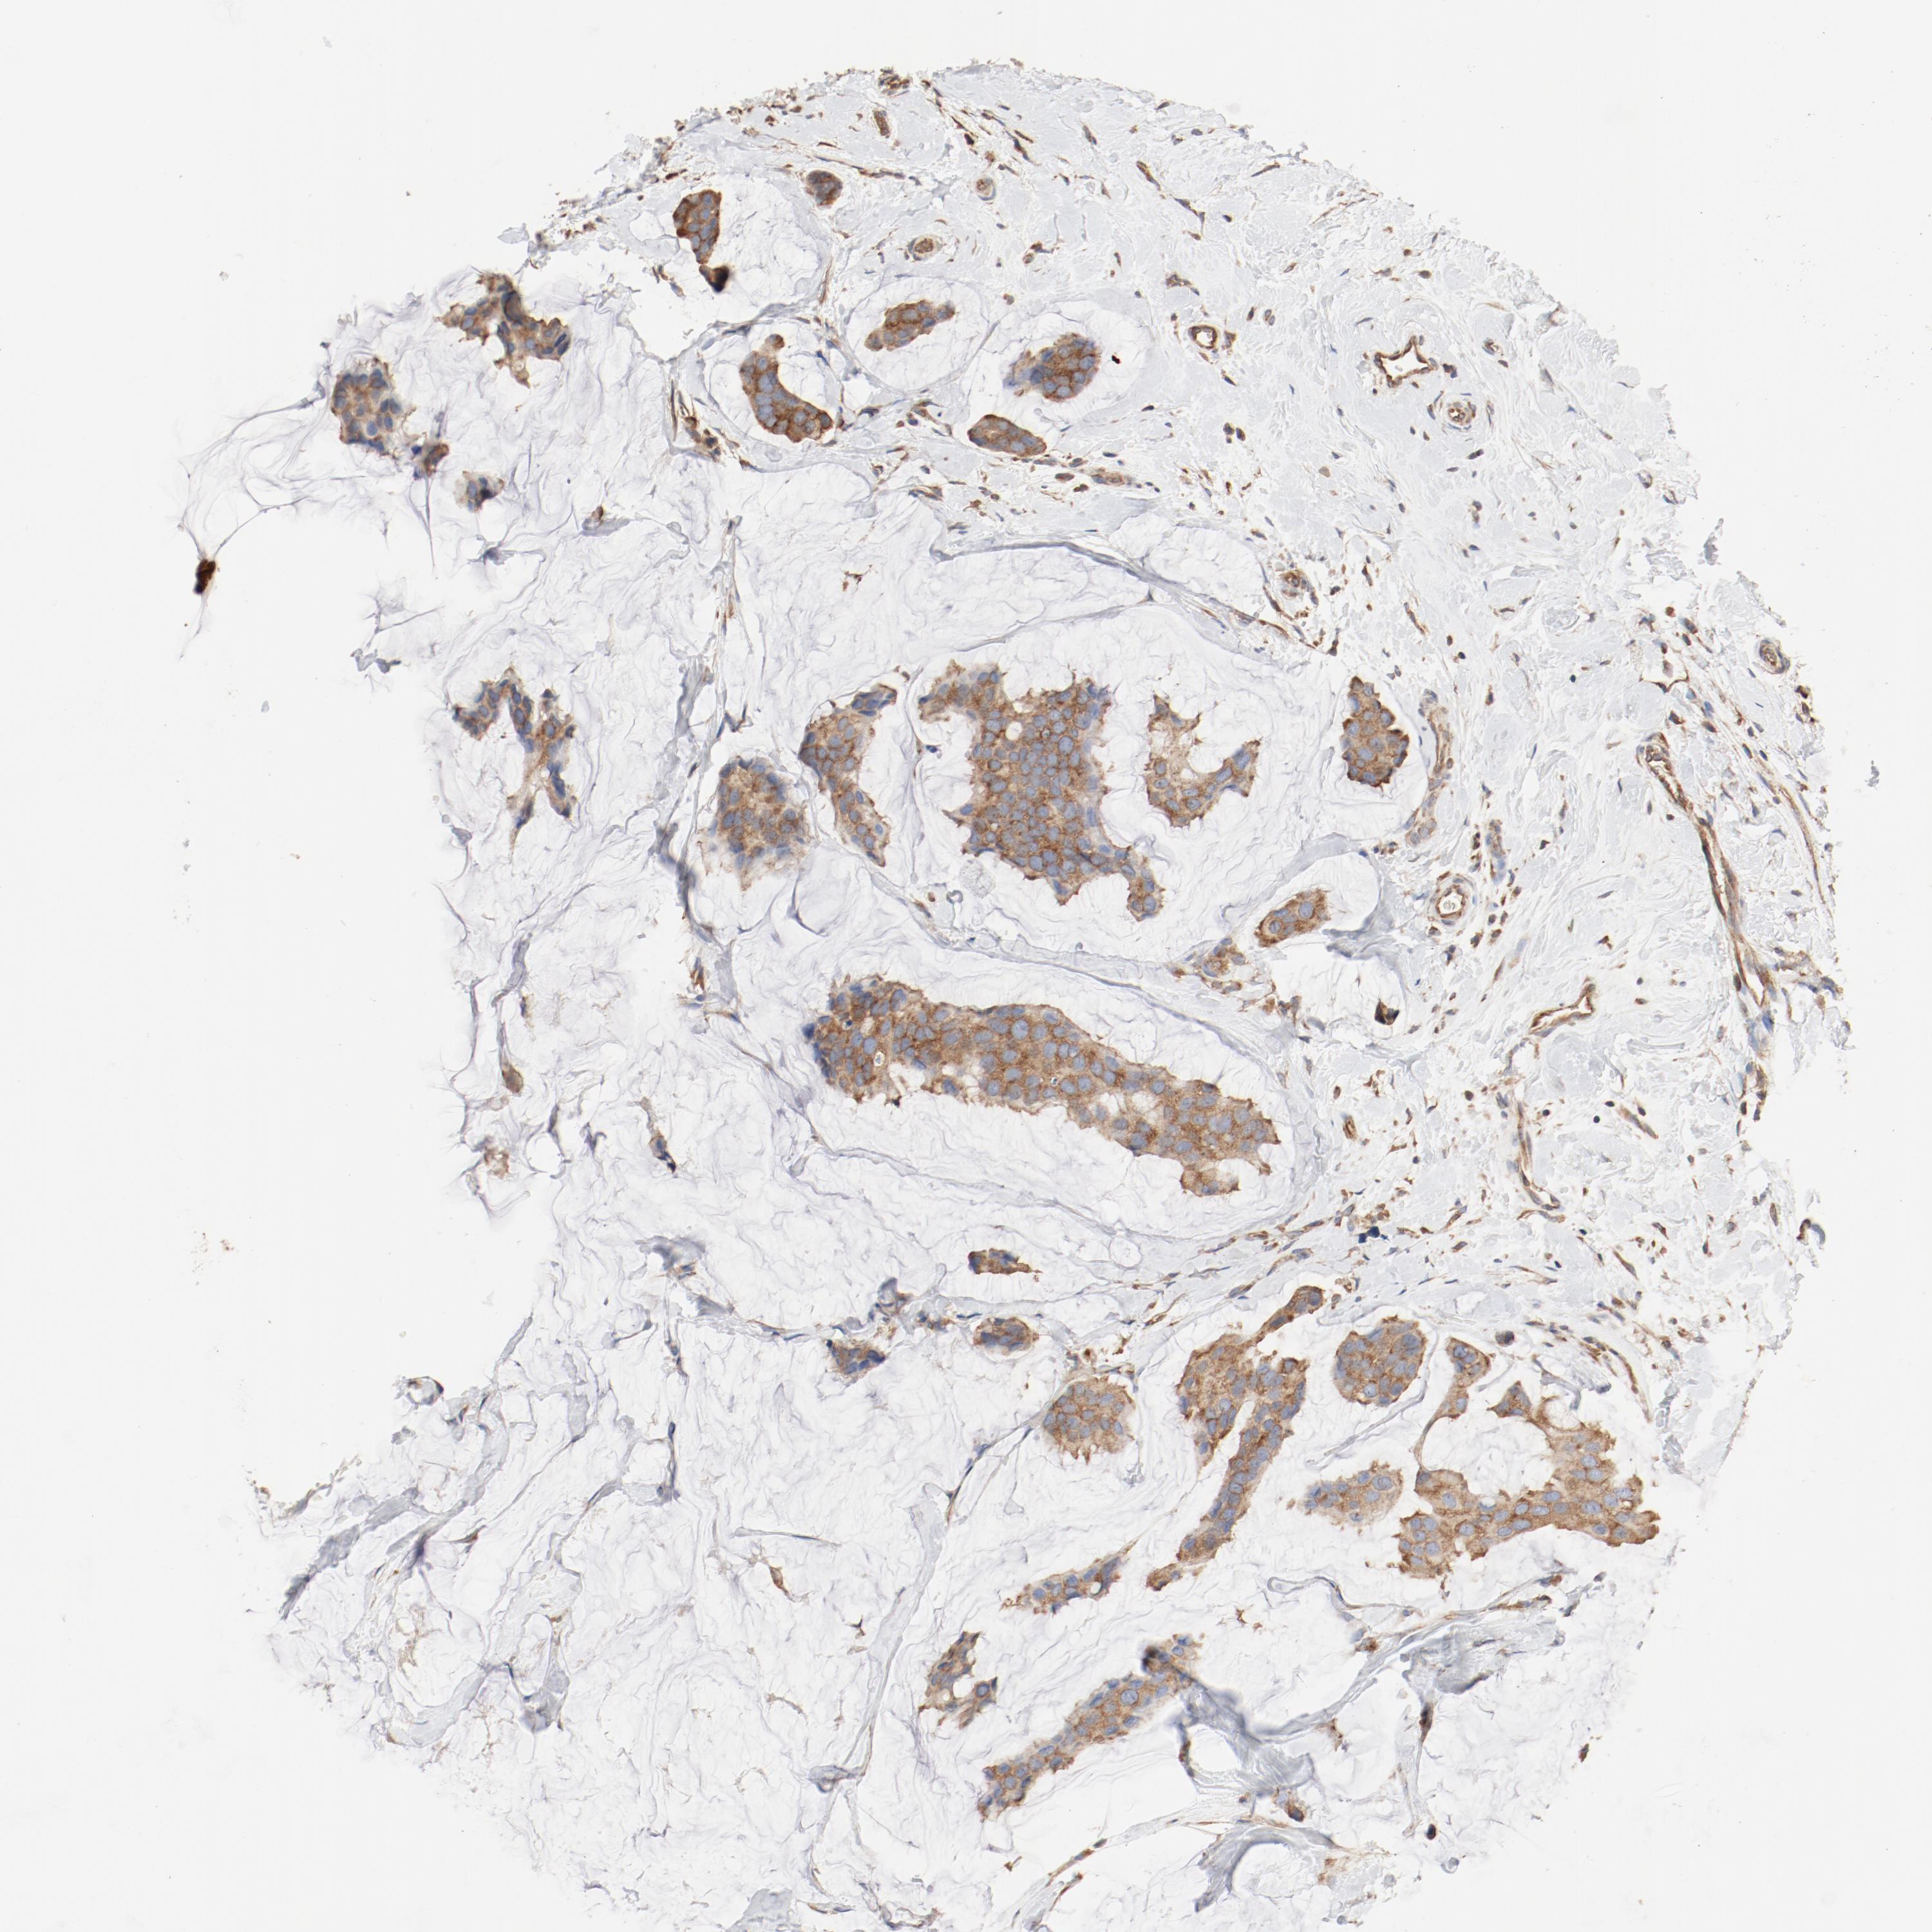

CANCER BREAST CANCER Show tissue menu

BRCA TCGA BRCA VALIDATION PROTEIN EXPRESSION

ANTIBODIES

AND

VALIDATION